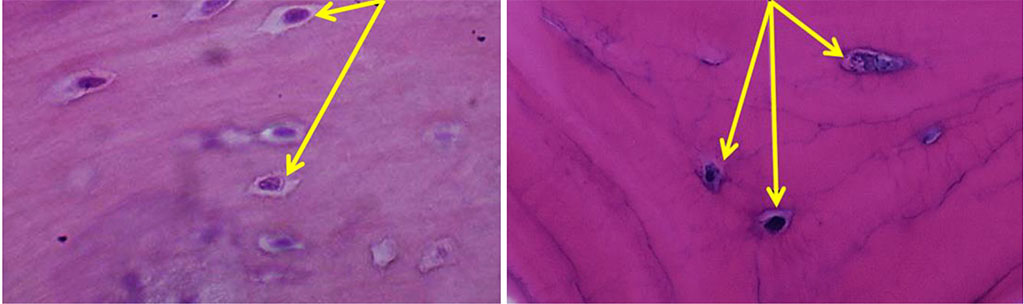

The histological examination of the bone biopsies taken from the chin symphysis area and from the area of the mandible outer oblique line has revealed that the bone tissue features a well-defined cortical plate and spongy bone. The inter-rod space is filled with bone marrow reticular stroma with no foci of hematopoiesis and with areas of rough-fiber based poorly shaped connective tissue. The cortical bone mass is of a lamellar structure with well-shaped Haversian canals. Osteons are short, based along the bone surface. Part of the trabeculae includes an inhomogeneous bone matrix, where the trabeculae internal structure features a bone matrix with empty lacunae, as well as with clefts and stratified areas of bone matter. The surface of the rods contains bone tissue with osteocytes, with areas of immature bone tissue occurring sometimes. The inner surface of the Haversian canals and the outer surface of the trabecular part feature signs of smooth resorption, which reveal themselves as splitting bone substance. The inter-rod space is filled with loose fibrous unshaped connective tissue. The trabeculae of the autograft spongy bone have a horizontal orientation, with a mature structure with individual osteoids and proliferating osteoblasts with no osteoclasts. In most cases, the Haversian canals do not contain vessels. As for the chin symphysis area, the spongy layer is basically not to be seen, and the bone tissue appears as a compact layer of homogeneous, dense bone, while in the outer oblique line area, the spongy layer was observed to have a rough-grained pattern. Osteocytes located among the fibrous bone matrix are of a stellate shape, their nuclei located in the central part of the cells (Fig. 9).

Figure 9. Osteocytes on histological preparations of the intact bone from the chin symphysis area (a) and from the outer oblique line area (b); (×800, hematoxylin-eosin stain).

Osteocytes from the chin symphysis area are oriented along the bone plate course, whereas osteocytes from the outer oblique line area – along the circles around the Haversian canals (Fig. 10).